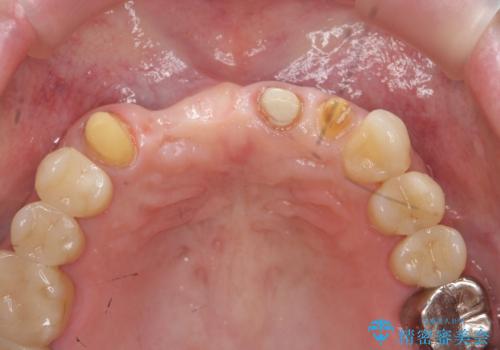

- ブリッジの根元が折れ、審美性の改善・治療を求めて来院されました。

保存の難しい歯を抜去しロングブリッジによる補綴を選択しました。

かみ合わせの観点からインプラント治療は難しく、入れ歯も希望されなかったためブリッジによる補綴を選択しました。